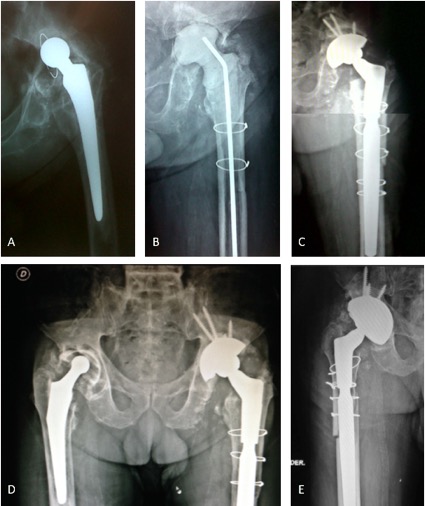

Introducción: El objetivo de este estudio es analizar nuestros resultados clínico-radiológicos con el uso de copas de tantalio trabecular para la reconstrucción de acetábulos complejos, tanto en cirugías primarias como en revisiones, y com- pararlos con series similares de otros autores. Materiales y Métodos: Se llevó a cabo una revisión retrospectiva de una serie de 42 cirugías (29 revisiones y 13 artro- plastias primarias) en 40 pacientes, entre marzo de 2010 y marzo de 2016. La serie incluyó a 20 mujeres y 20 hombres, con una edad promedio de 60 años (rango 27-93). El seguimiento promedio fue de 37 meses (rango 12-84). Todos los pacientes fueron tratados con el mismo tipo de metal trabecular. Resultados: Al promedio de seguimiento mencionado la supervivencia del componente acetabular fue del 97,6%. Un paciente fue tratado con artroplastia de resección debido a una infección persistente. La tasa de complicaciones totales fue del 12% y el promedio del Harris Hip Score posoperatorio fue de 81,54 (rango 63,25-92,75). Conclusiones: Aunque se necesita un seguimiento más prolongado, el uso de copas de metal trabecular logra resultados prometedores para el tratamiento de acetábulos complejos.